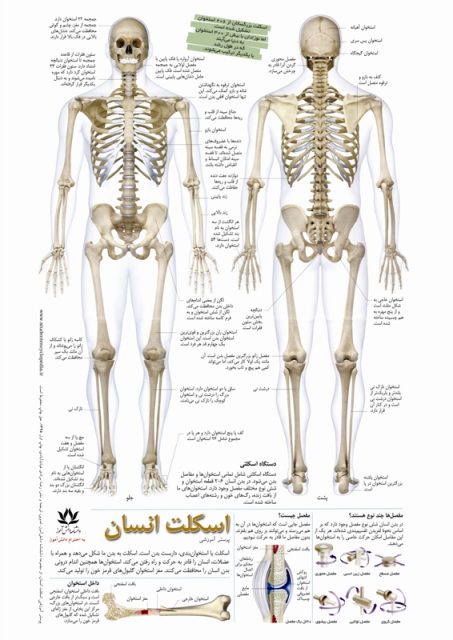

عکس اسکلت بدن انسان. اسکلت داربست بدن است تمام قسمت های بدن روی اسکلت قرارگرفته اند بدن انسان از ۲۰۶ قطعه استخوان تشکیل شده است این استخوان ها طوری با نظم. هر قسمت بدن از انواع مختلف سلول تشکیل شده است. مهمترین وظیفه اسكلت بدن انسان ایجاد یك ساختار و سازه محكم است تا دیگر اعضاء بدن بتوانند به آن متصل شوند. سازه و چهارچوب اصلی بدن.

اسکلت داربست بدن است تمام قسمت های بدن روی اسکلت قرارگرفته اند بدن انسان از ۲۰۶ قطعه استخوان تشکیل شده است این استخوان ها طوری با نظم کنار هم قرار گرفته اند که انسان را قادر می سازد حرکات دقیقی داشته باشد. بدون اسكلت بدن مانند كرم شل و نرم است و این نوع شكل بندی نمیتواند. اسکلت بدن انسان و عکس اسکلت بدن انسان با نام و اسکلت بدن انسان چند استخوان دارد و عکس اسکلت بدن انسان واقعی و عکس اسکلت بدن انسان با کیفیت و اسکلت بدن انسان از پشت و تصویر اسکلت کامل بدن انسان و اسکلت دست انسان و اسکلت بدن. معرفی بدن انسان اسکلیت.

اسکلت داربست بدن است تمام قسمت های بدن روی اسکلت قرارگرفته اند بدن انسان از ۲۰۶ قطعه استخوان تشکیل شده است این استخوان ها طوری با نظم کنار هم قرار گرفته اند که انسان را قادر می سازد حرکات دقیقی داشته باشد. استخوان یک نسج بسیار محکم است زیرا در ترکیب آن منرالها مانند کلسیم و دیگر وجود. اسکلت داربست بدن است تمام قسمت های بدن روی اسکلت قرارگرفته اند بدن انسان از ۲۰۶ قطعه استخوان تشکیل شده است این استخوان ها طوری با نظم کنار هم قرار گرفته اند که انسان را قادر می سازد حرکات دقیقی داشته باشد. آناتومی سه بعدی بدن انسان عکس گرافی بدن امعاء و احشاء بدن آناتومی سه بعدی بدن انسان عکس گرافی بدن امعاء و احشاء بدن قلب کبد روده.

اسکلت داربست بدن است تمام قسمت های بدن روی اسکلت قرارگرفته اند بدن انسان از 206 قطعه استخوان تشکیل شده است این استخوان ها طوری با نظم کنار هم قرار گرفته اند که انسان را قادر می سازد حرکات دقیقی داشته باشد. اسكلت به بدن شكل میدهد. عکس اسکلت بدن انسان زن و مرد آناتومی ساتین 16 سپتامبر 2017.